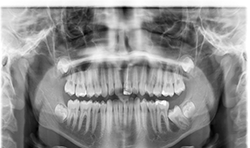

Case 1: 12-year-old boy with delayed eruption of the mandibular left second molar

The panoramic radiograph (Fig. 1) shows a well-defined, corticated, radiolucent area mesial to the mandibular left second molar. The inferior alveolar nerve canal is displaced inferiorly.

CBCT images of the same patient (Figs. 2A, 2B, 2C) reveal the lesion extends mesial to the third molar follicle, displacing the thinning buccal cortex. The lesion arises from the cementoenamel junction (CEJ) of the second molar. The inferior alveolar nerve canal is intact. The lesion was treated by surgical removal and submitted for histological examination. The histopathologic diagnosis was a dentigerous cyst.